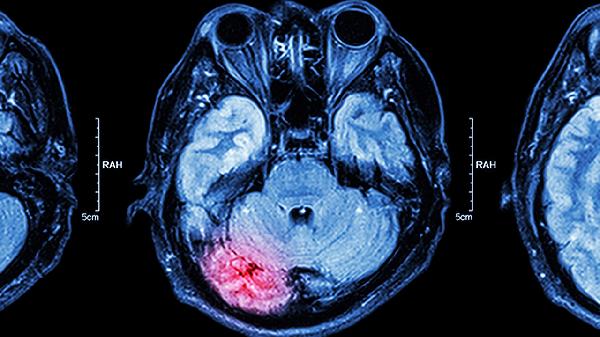

核磁共振检查能够发现早期脑肿瘤,检出率受肿瘤大小、位置、影像分辨率等因素影响。核磁共振对脑肿瘤的早期诊断具有较高敏感性,主要通过组织对比度差异、多序列成像技术、增强扫描效果、功能成像辅助以及定期随访对比五种方式提高检出率。

核磁共振利用氢原子在磁场中的信号差异成像,脑肿瘤组织与正常脑组织在T1加权像、T2加权像上呈现明显信号差异。例如胶质瘤在T2像表现为高信号,脑膜瘤在增强扫描中呈现均匀强化,这种对比度差异可帮助识别直径小至3-5毫米的早期病灶。

静脉注射钆对比剂后,血脑屏障破坏区域会出现明显强化。约80%的恶性脑肿瘤在早期即可出现异常强化,垂体微腺瘤等病灶在动态增强扫描中表现为延迟强化,这些特征有助于发现常规平扫难以识别的微小肿瘤。